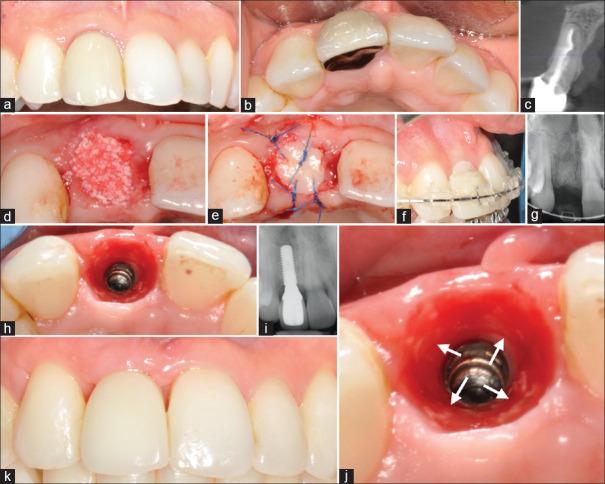

The long-term safety of xenografts and their potential association with disease are valid concerns. Bovine bone substitutes which are by far the most commonly used xenografts in dentistry are not biodegradable. The aim of the present report was to raise awareness on the long-term risks of the bovine-derived xenografts. Patients who experienced clinical complications after xenografting are reported. Patients' demographic, significant medical, and dental findings are reported. Complications included migration/encapsulation/displacement of the graft material, chronic inflammation, and soft-tissue disturbances/fenestrations. Albeit some xenograft complications are not significant enough to compromise the initial outcomes achieved, the xenografted particles seemed to be left intact favoring conditions for migration. The authors observed the inability of the human host to biodegrade the xenograft particles. The intact/migrated bovine bone particles present a risk to patients and may contribute to long-term clinical complications in implant dentistry.